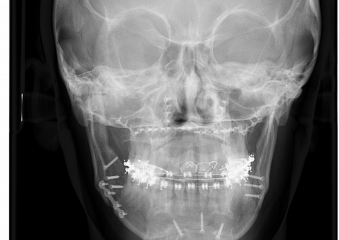

Telerradiografia Frontal Inicial - Clínica Cliniface

Telerradiografia Frontal Inicial

Telerradiografia Frontal após a cirurgia - Clínica Cliniface

Telerradiografia Frontal após a cirurgia